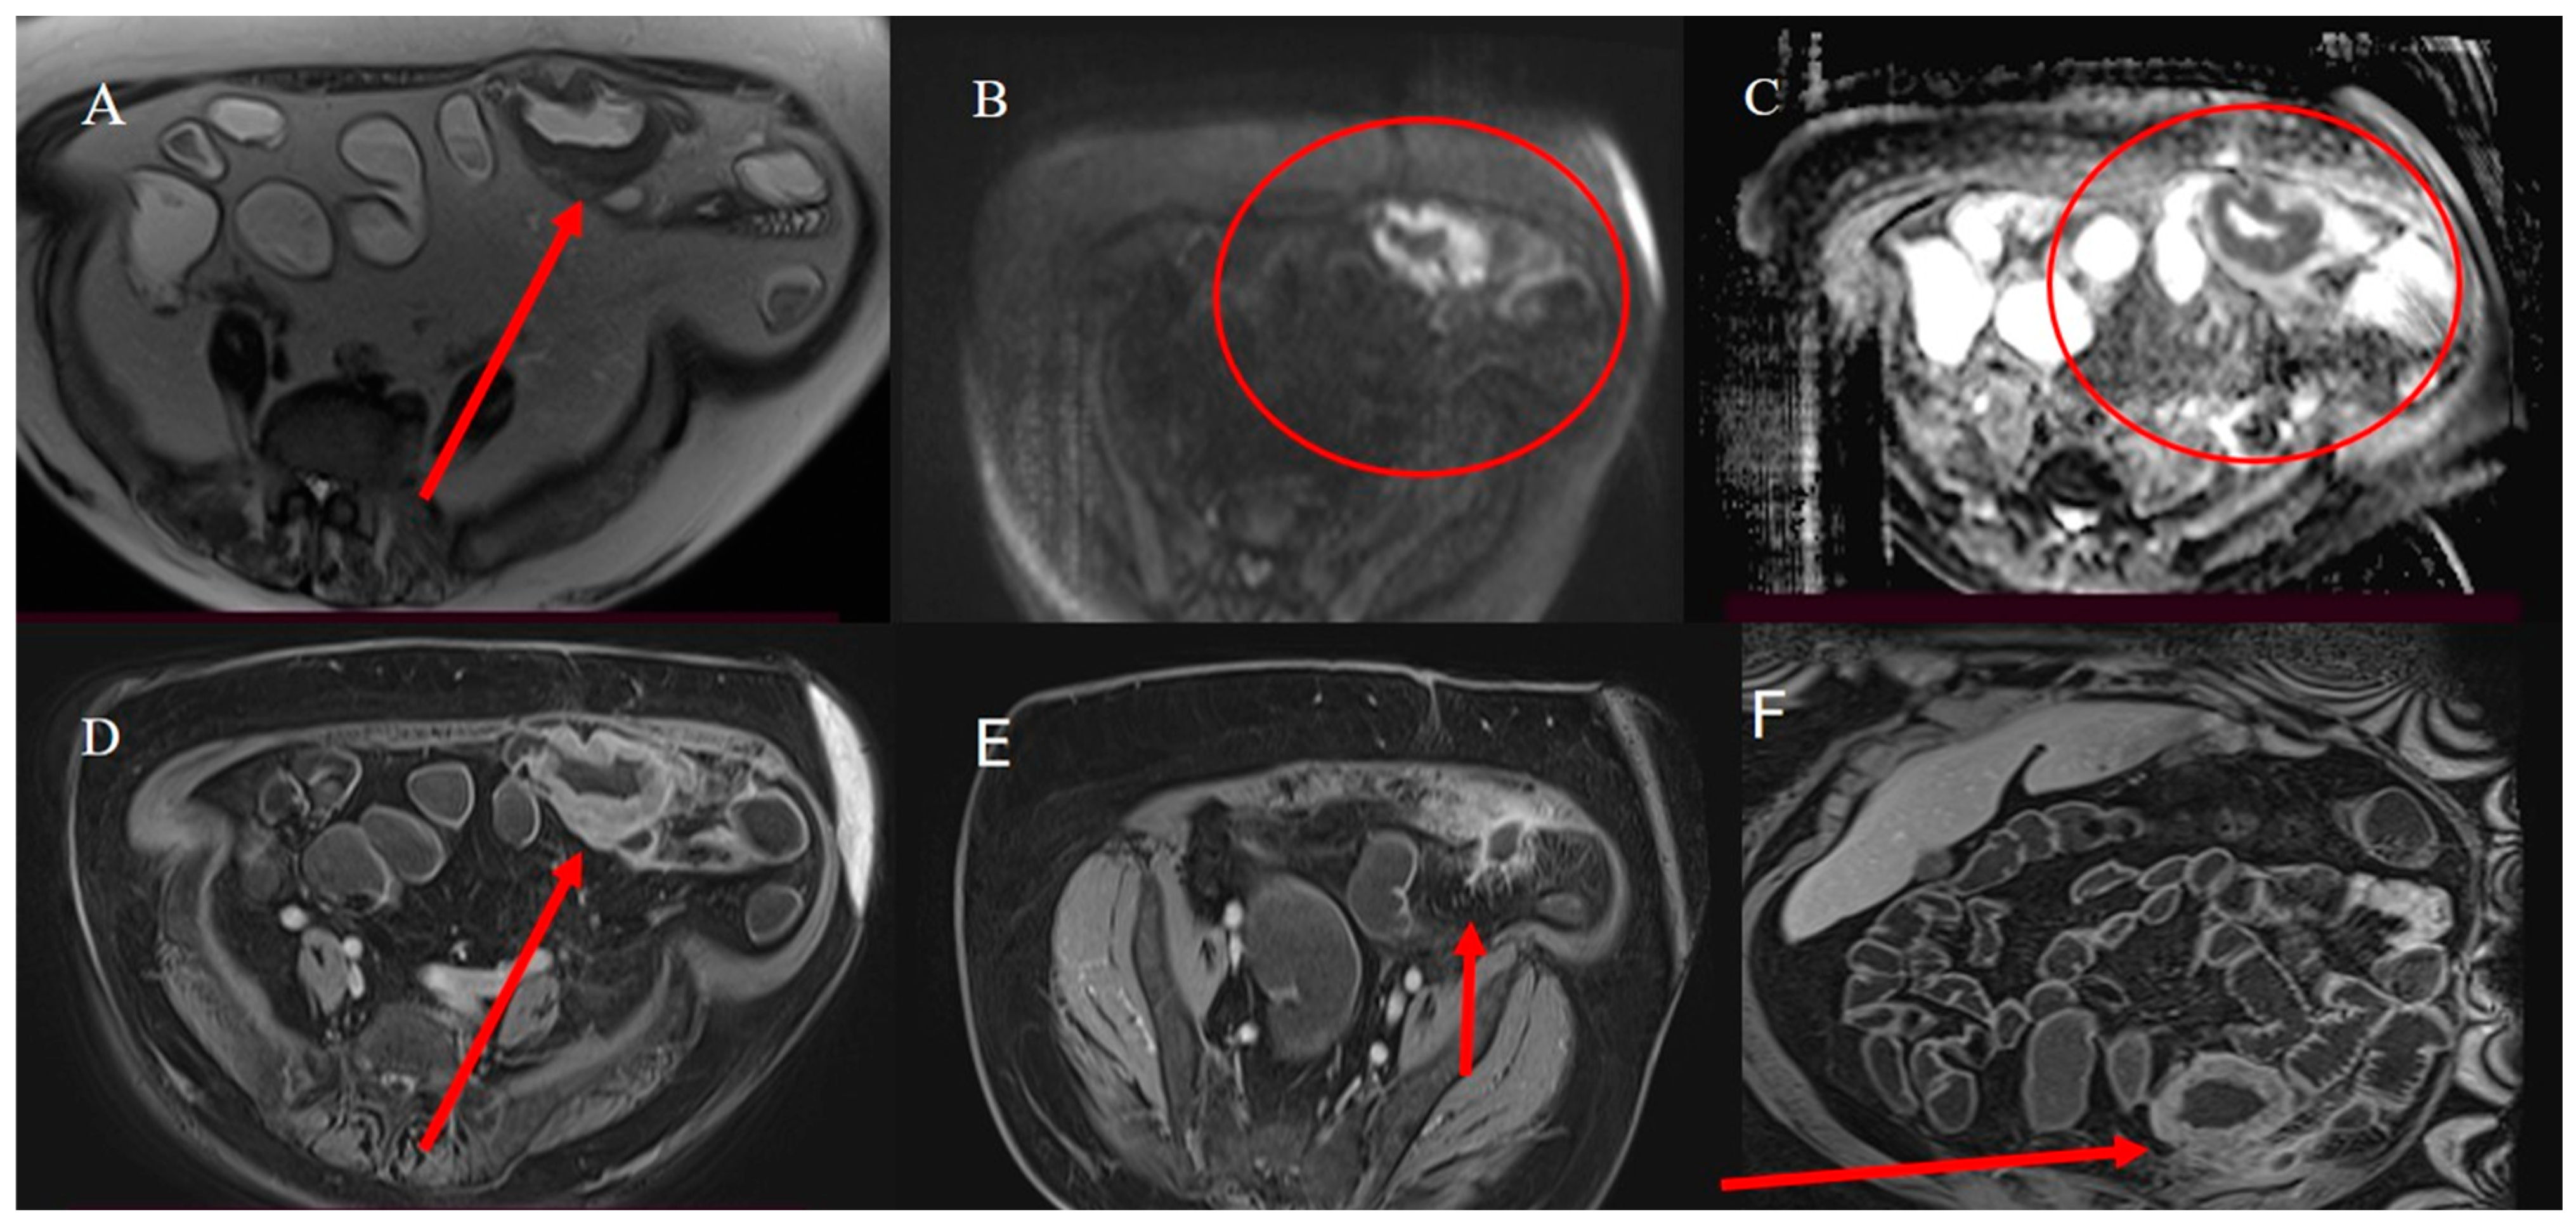

2.3. Small Bowel Tumor Presentation in Emergencies with Intestinal Intussusception

2.6. Small Bowel Tumors Mimicking Inflammatory Disease

2.7. Metastatic Presentation of Small Bowel Tumors